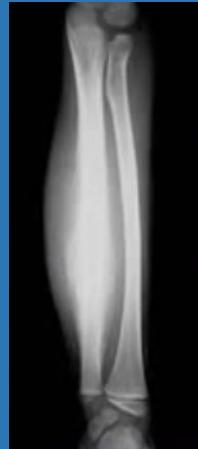

| Open Fracture | A fracture with a breach in the overlying skin and soft tissues, creating communication with the external environment. All open fractures are considered contaminated (even small punctures; aka compound fracture). Causes: Can result from high-energy trauma (RTAs, falls, firearms; signs: degloving, crush syndrome, bone loss, segmental) or low-energy trauma. Contamination risk higher with farm/soil injuries, bites, delayed presentation (>12h), fecal/oral/soil/water exposure. Mechanism: Low/high velocity missiles (cavitation >300 m/s); in-out (cleaner) vs. out-in (dirtier). Gross/Clinical: ![]() | History: Mechanism of injury (energy, time, place, type/impact method), consciousness, wound size/bleeding amount, other injuries (often missed), tetanus status. Assessment: ATLS protocol (ABCDE) first (treat patient, not fracture; exclude shock/brain injury, monitor vitals; viscera exam: ribs=lungs/liver/spleen, pelvis=bladder/urethra). Examine wound (look/feel/move carefully post-splint), check distal neurovascular status, compartment syndrome. Photograph/remove gross contamination; cover with saline dressing. Classification (Gustilo-Anderson): - Type I: <1 cm wound, clean, minimal soft tissue. - Type II: >1 cm wound, moderate soft tissue (no stripping). - Type IIIA: Extensive soft tissue damage, but adequate bone coverage. - Type IIIB: Extensive soft tissue loss with periosteal stripping; bone exposed, requires flap coverage. - Type IIIC: Any open fracture with an arterial injury requiring repair. | Initial (ER): ATLS first. Cover wound with sterile saline-soaked dressing, splint limb, IV fluids (request blood if needed); traction if no distal pulse/deformity. Prophylaxis: Tetanus prophylaxis/serum and broad-spectrum IV antibiotics immediately (culture tissue/blood); clean major contamination. Surgical: Urgent debridement/irrigation within 6-12h (“Dilution is the solution to pollution”; pulse-irrigate 3-6-9L saline; excise non-viable tissue/foreign material, trim skin edges, remove dead muscle/detached bone, preserve N/V). Stabilization: external fixator (preferred severe; replace with cast post-infection); internal if clean/minimal. Wound closure delayed (primary if small/clean; secondary if contaminated/large). Early soft tissue cover. | The diagnosis is typically obvious. Key: Classify severity; identify associated injuries like compartment syndrome, vascular damage, or high-energy signs (e.g., crush). Differentials for contamination: Primary (field debris) vs. secondary (post-fixation if poor debridement). | Complications: Infection (cellulitis, osteomyelitis, chronic with sequestra/drainage, gas gangrene), tetanus; higher with delay/exposure/bites. - embolisms fat, thrombi others.. Case Insight: Unconscious patient (e.g., open tibia post-RTA): ABCDE/cervical collar, distal pulses/traction, admit for debridement; ankle fall: Splint post-ABC, assess neurovascular. |